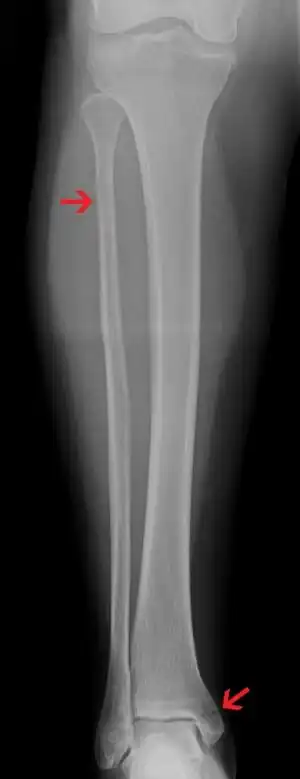

Maisonneuve fracture

| A Maisonneuve fracture with arrows marking the location of the two fractures | |

A Maisonneuve fracture is an injury at the ankle with an associated break of the lower leg near the knee.[5] The ankle injury involves a tear of the ligament connecting the two bones of the lower leg, the tibiofibular syndesmosis.[5] There may also be a break of the medial malleolus or rupture of the deltoid ligament of the ankle.[3] Symptoms typically include tenderness over the medial ankle and outside aspect of the upper part of the lower leg.[1]

It typically results from excessive external rotation of the ankle.[3] X-rays typically show widening of the ankle joint, though this may be subtle.[3][1] Stress views may be useful in unclear cases.[4] People may not mention pain around the knee due to the greater degree of pain in the ankle.[6] It is classified as a type C3 ankle fracture according to the Danis-Weber classification system.[7]

Ankle Xrays are used to detect widening of the tibiofibular syndesmosis or medial clear space. The medial clear space is the area between the talus of the ankle and the medial malleolus. Damage to the deltoid ligament and syndesmotic ligaments result in mortise instability, causing the talus to laterally shift and widen the medial clear space.[9][16] A study found that the medial clear space size of a normal ankle and an injured ankle measured at 4 millimetres and 5.4 millimetres in length respectively.[14] To confirm diagnosis, full-leg radiographs are used to inspect for fractures of the proximal fibula and widening of the interosseous clear space (or tibiofibular clear space). The interosseous clear space is the area between the medial side of the fibula and lateral side of the tibia. A peer-reviewed study, published in Injury in 2004, found that an interosseous clear space greater than 10 millimetres indicates diastasis of the syndesmotic ligaments.[9]